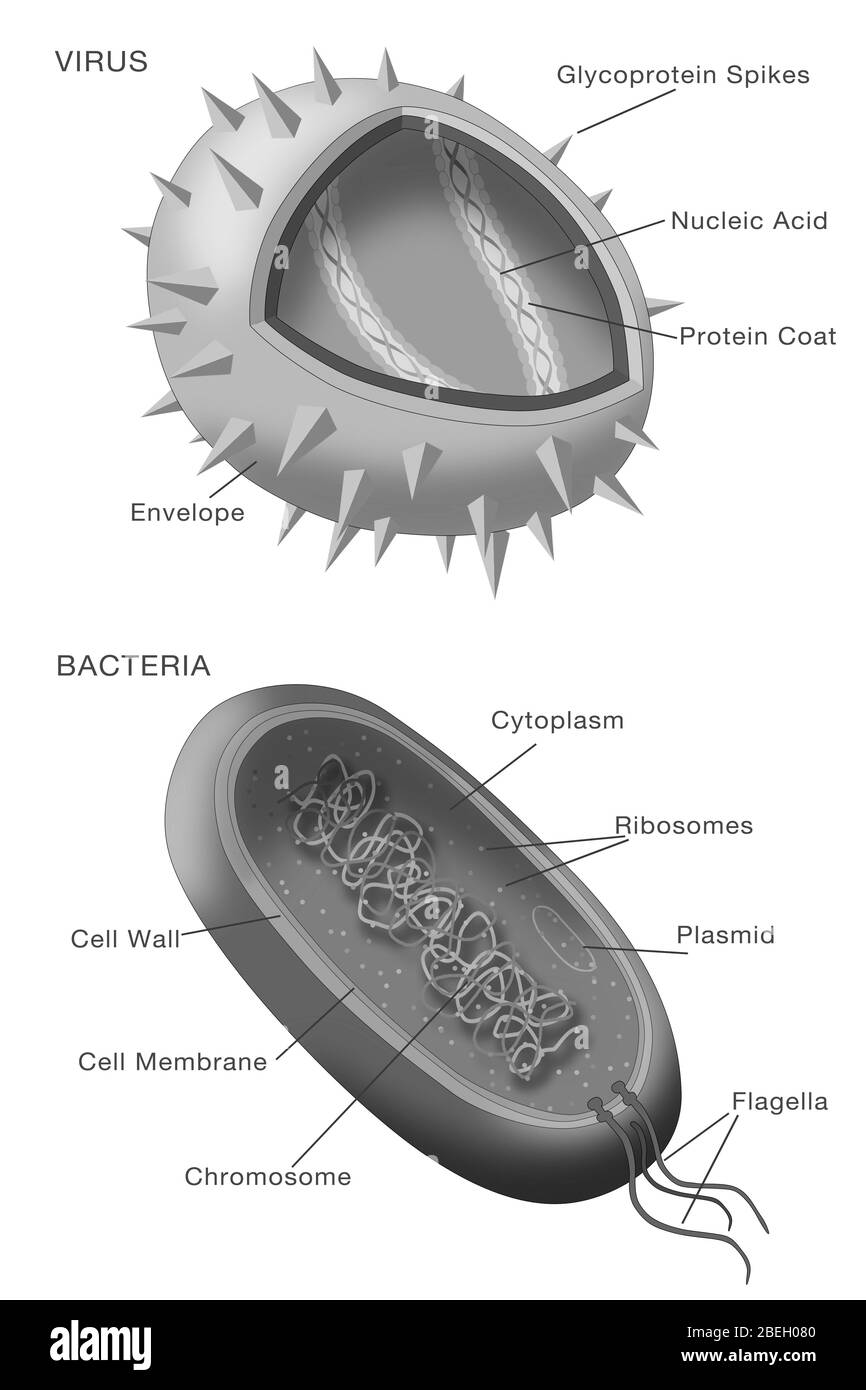

Diagramme des virus et des bactéries Banque D'Imageshttps://www.alamyimages.fr/image-license-details/?v=1https://www.alamyimages.fr/diagramme-des-virus-et-des-bacteries-image353185952.html

Diagramme des virus et des bactéries Banque D'Imageshttps://www.alamyimages.fr/image-license-details/?v=1https://www.alamyimages.fr/diagramme-des-virus-et-des-bacteries-image353185952.htmlRM2BEH080–Diagramme des virus et des bactéries